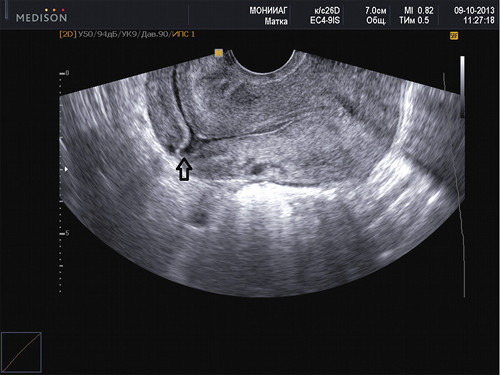

Ультразвуковое исследование (УЗИ) является ключевым методом для диагностики рубцовой недостаточности. В процессе проведения данного обследования специалист обращает внимание на следующие аспекты:

- общее состояние операционного шва;

- наличие пустот, вмятин, выпуклостей (лигатур) и мелких разрывов в области шва;

- толщину рубцовой ткани;

- возможные патологические изменения слизистой оболочки в месте наложения шва.